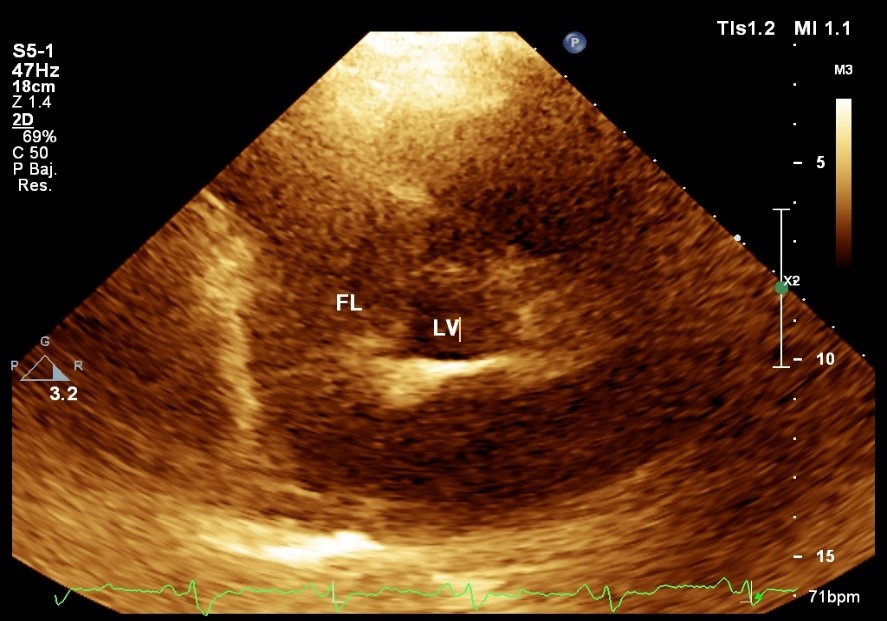

En el ecocardiograma se observó el ventrículo izquierdo sin dilatación, con hipertrofia ligera y motilidad global conservada. Las válvulas presentaron cambios degenerativos, fundamentalmente la aórtica trivalva. La raíz aórtica estaba dilatada por el colgajo íntimo, móvil (visto como imagen de ecogenicidad baja); en sístole, este se desplazaba hacia la pared, y en diástole hacia el anillo valvular. El chorro de regurgitación era moderado, central, limitado por la interposición del colgajo íntimo.

El ventrículo izquierdo presentó un patrón de relajación pseudonormal, y el del flujo pulmonar era tipo II. Se vio además un derrame pericárdico posterior, ligero. No se encontraron trombos intracavitarios. La aorta midió 52 mm; la aurícula izquierda 44 mm; el ventrículo izquierdo 50/31 mm; el tabique interventricular 11 mm; la pared posterior 11 mm. El tiempo de aceleración de la arteria pulmonar fue de 100 ms; y la fracción de eyección ventricular izquierda de 68 % (Fig. 1).

Fig. 1 – Ecocardiograma de vasos grandes, en eje corto paraesternal. Obsérvense la luz falsa aórtica, y la verdadera.